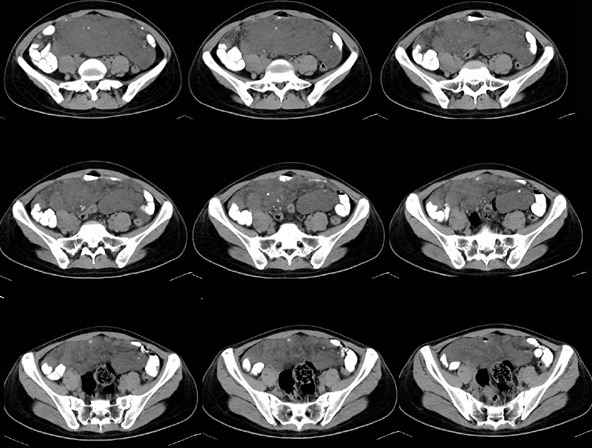

女性,28岁,停经3月,腹部膨隆1月,产前检查发现腹部占位

{肿块中心ct值27hu,增强后,动脉期、门脉期均无明显强化)

1 肠系膜肿块诸期无明显强化,肠系膜血管包绕其中但其周围仍见脂肪称“脂肪环征”;2 肠系膜血管远端较近端细,于重组像上见血管周围有强化结节为炎性结节,3肿块内见部分脂肪密度及少许点状钙化。4 腹膜后无肿大ln。

需与恶性病变鉴别,脂肪环征为重要点。亦需与卵巢源性肿瘤鉴别,年龄以及未见“卵巢静脉征”为要点。

患者手术病理:腹腔囊性淋巴管瘤,象这样充满整个腹腔的的确很少见